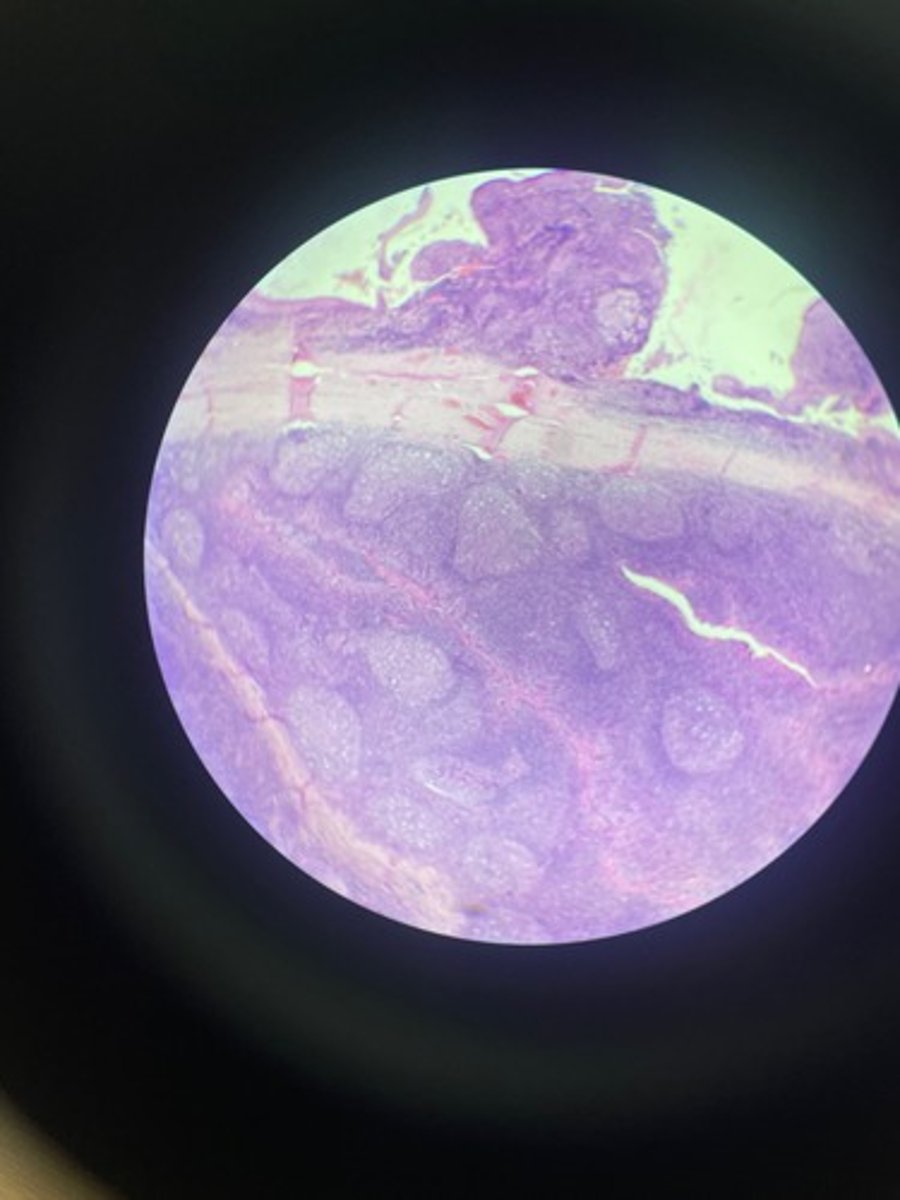

Thymus HE

Thymus HE

Thymus HE

Thymus HE

Thymus HE

Thymus HE

Thymus HE

Thymus HE